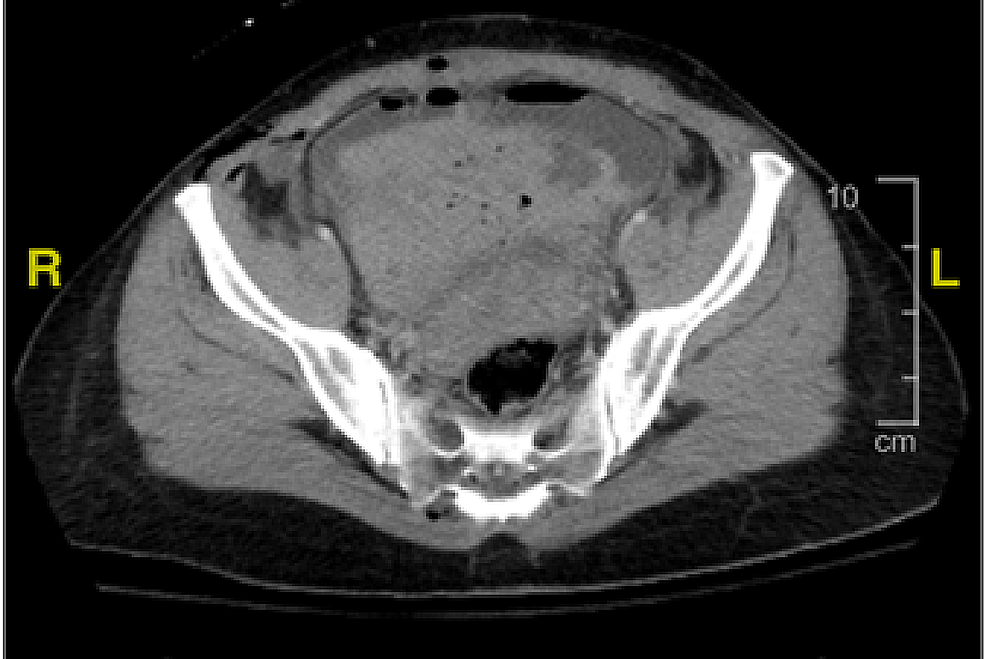

From www.cureus.com

Cureus Cesarean Section Complications Followed by Bladder Cystotomy Are Blood Clots Common After C-Section probably the most feared complication of cesarean delivery deliveries is the formation of blood clots in the. identifying the signs of a blood clot after a c section. some postpartum bleeding and blood clots are normal in the days and weeks after giving birth. today, we now know the exact opposite is true: Women should remain. Are Blood Clots Common After C-Section.